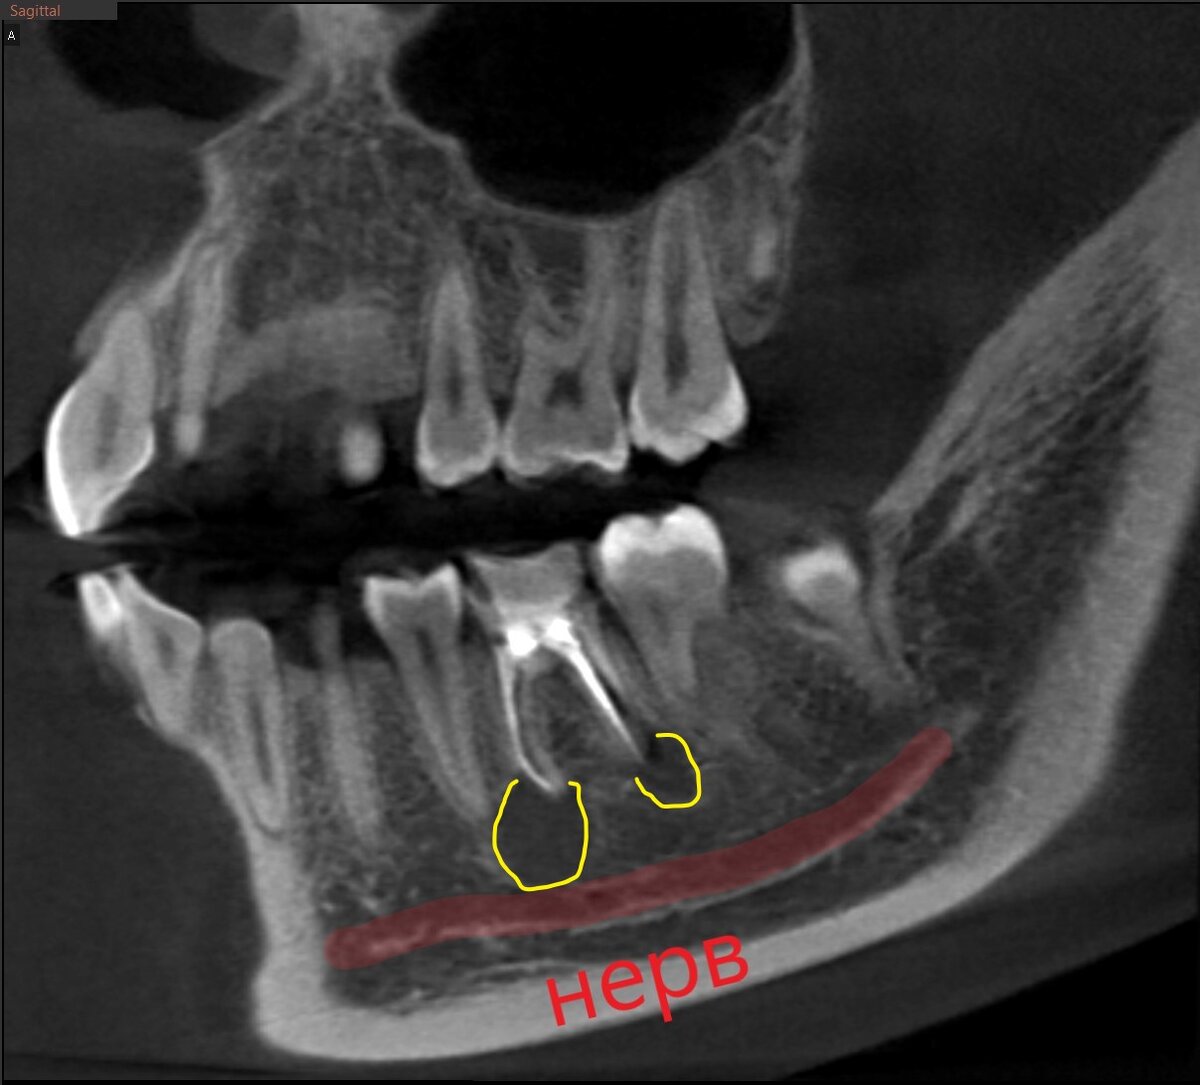

Анатомия зубов: мезиальный и дистальный корни